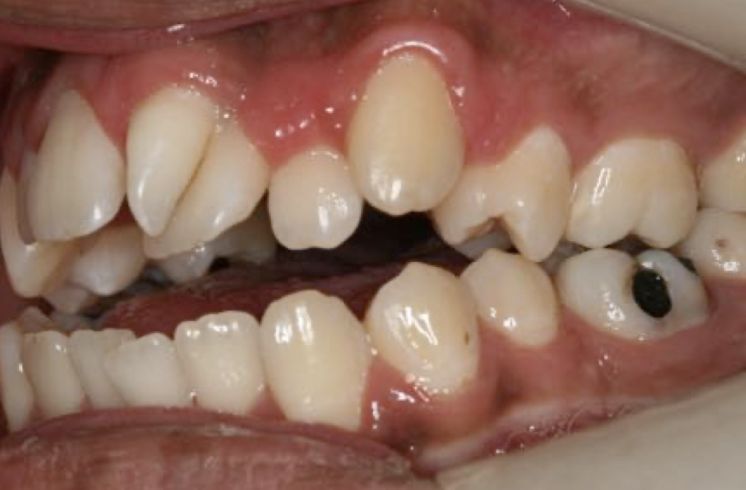

What dental anomaly does this patient have?

Transposition